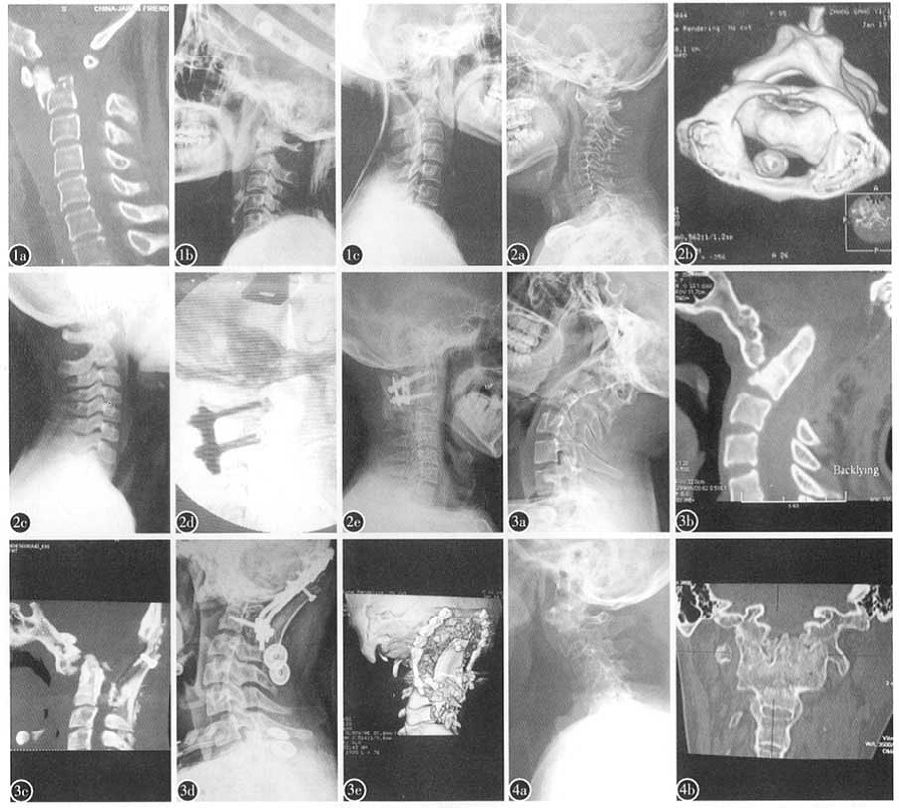

168例患者中,T1型71例(43%)(图1),其中新鲜创伤63例,慢性咽部炎症所致8例。T2型66例(38%)(图2),其中枕颈畸形26例,齿状突不连19例,创伤9例,肿瘤9例,结核3例。O型28例(17%)(图3),其中枕颈畸形1l例,创伤11例,医源性不稳4例,齿状突不连2例。I型3例(2%)(图4),均为强直性脊柱炎患者。

图1 a术前CT示新鲜齿状突基底部骨折脱位,属T1型寰枢椎脱位b经颅骨牵引复位后颈椎侧位X线片示寰枢椎脱位复位c复位后颈托外固定12周,颈椎侧位片示齿状突基部骨折线模糊,有骨痂生长

图2 a术前侧位x线片示齿状突不连.C1—2脱位伴鹅颈畸形,属,I'2型寰枢椎脱位b术前CT片示齿状突不连,C1~2严重脱位c术前牵引2周后侧位x线片示寰枢椎脱位基本复位d采用椎弓根钉技术使C1—2脱位解剖复位,并固定融合e术后6个月侧位X线片示植骨融合

图3 a术前颈椎侧位X线片示颅底凹陷,寰椎向前下方脱位至C2/3椎间盘水平,牵引2周不能复位,属0型寰枢椎脱位b术前颈椎CT片示颅底凹陷,寰椎向前下方脱位至C2/3椎间盘水平,枢椎齿状突突入颅内,枕骨

寰椎后弓和枢椎椎板被前次手术切除至缺如c经前路松解,一期后路C0—2椎弓根钉器械复位固定融合术后CT片示齿状突复位d术后颈椎侧位X线片示齿状突复位,鹅颈畸形矫正e术后颈椎三维CT片显示寰枢椎复位,内固定、植骨位置良好

图4 a强直性脊柱炎患者颈椎侧位X线片示寰枢椎脱位强直b颈椎三维CT片显示寰枢椎关节突关节已融合强直,属I型脱位